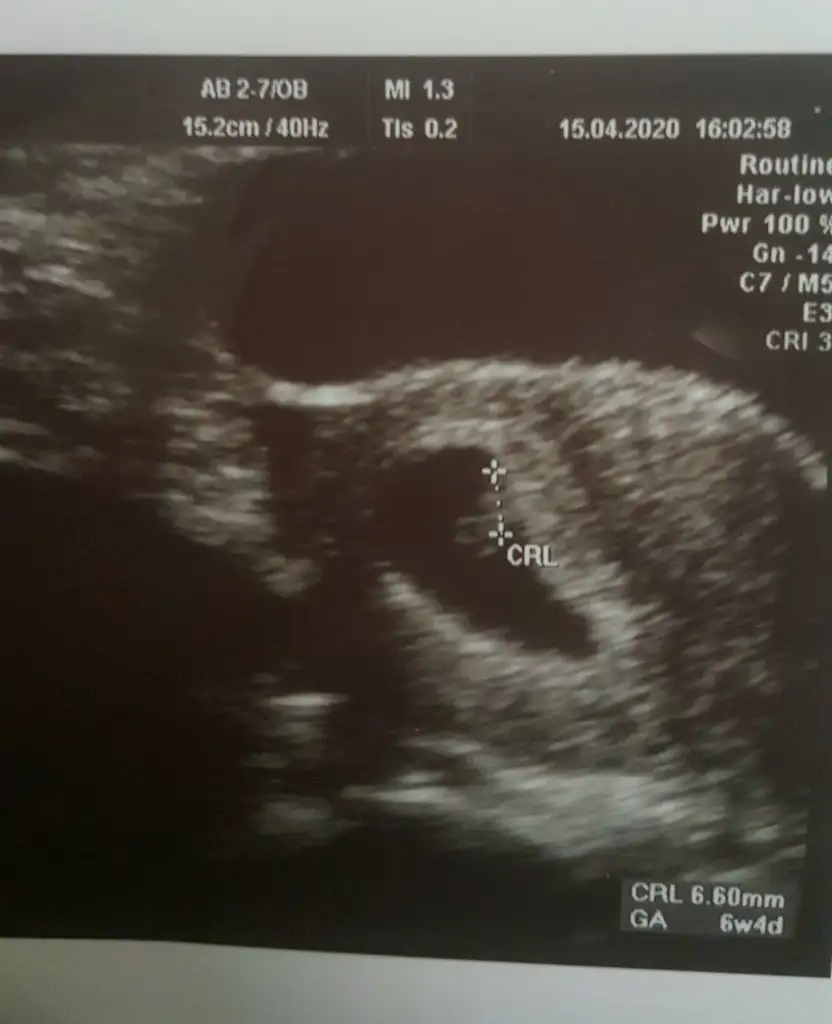

Gozun aydin canim kokusunuda duyarsin melegin insallahSelamlarrben az önce doktordan geldim. Sonunda gördüm minik boncuğumu, 7+0 da hem keseyi hem kalp atışını duyabildik çok şükür

Her şey yolunda hiç bir sıkıntı yok dedi doktorumuz. Heyecandan soracağım ne varsa da unuttumresimdeki fasulye aklımı başımdan aldı resmen

Gozun aydin canim darisi basimizaKizlar cok mutluyum kendisinide gördük kalp atışınıda duyduk minigimin❤

Gozun aydin canim Allah kucagina almayi nasip etsin cok sevindim darisi kalp atisi bekleyenlereKizlar cok mutluyum kendisinide gördük kalp atışınıda duyduk minigimin❤